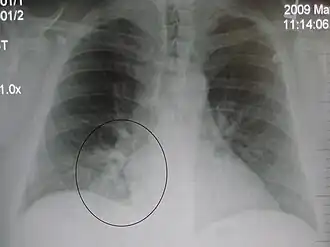

AP CXR showing left lower lobe pneumonia associated with a small left sided pleural effusion -

AP CXR showing right lower lobe pneumonia -

AP CXR showing pneumonia of the lingula of the left lung -

Right upper lobe pneumonia as marked by the circle. -

Left upper lobe pneumonia with a small pleural effusion.

Right lower lobe pneumonia as seen on a lateral CXR